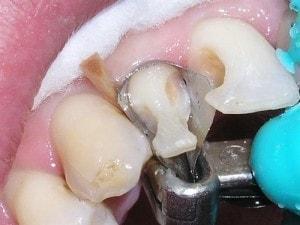

Caries in incisor teeth

Decay in teeth #'s 7, 8, and 10

Restoration complicated by overlap

Carles removed

Enamel tapered on both preps. Enamel taper includes the entire labial of tooth #7. Many call this an apple core prep.